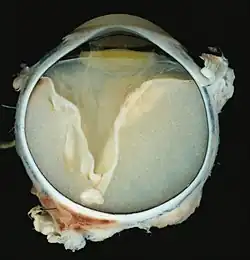

A case of Coats' disease, showing total retinal detachment with subretinal exudate containing cholesterol crystals and a fibrous nodule in the posterior pole

Grossly, retinal detachment and yellowish subretinal exudate containing cholesterol crystals are commonly seen.

Microscopically, the wall of retinal vessels may be thickened in some cases, while in other cases the wall may be thinned with irregular dilatation of the lumen.[11] The subretinal exudate consists of cholesterol crystals, macrophages laden with cholesterol and pigment, erythrocytes, and hemosiderin.[12] A granulomatous reaction, induced by the exudate, may be seen with the retina.[13] Portions of the retina may develop gliosis as a response to injury.